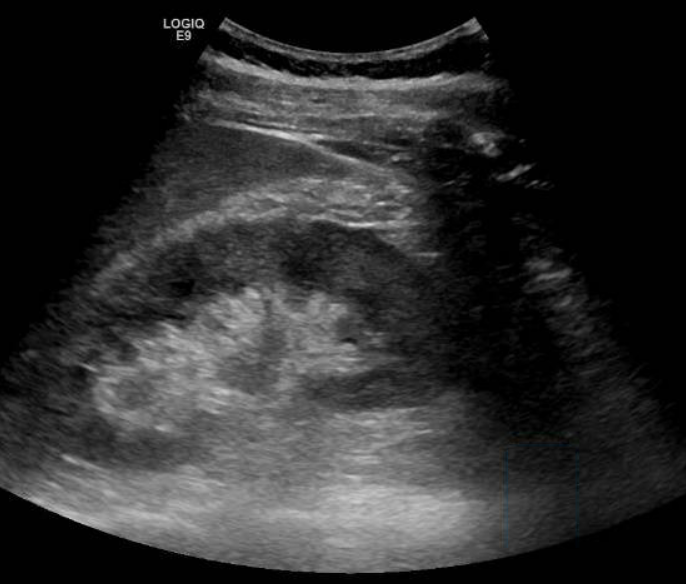

Se solicita ecografía abdominal que muestra líquido en espacio pararrenal posterior derecho bajo, sobre músculo psoasilíaco derecho, y leve ectasia piélica derecha sin identificar causa.

Entre las entidades que afectan al espacio pararrenal nos encontramos linfangioma, entidades fibróticas, hematomas, abscesos, neoplasias… Por tanto, se completa estudio con TAC abdominal con contraste. En el TAC se observa litiasis de 3 mm en meato ureteral derecho con dilatación pielocalicial grado II y leve-moderada cantidad de líquido en espacios retroperitoneales peri y pararrenal derechos, que se relacionan con salida de contraste intravenoso en fase excretora, compatible con rotura de la vía urinaria sin identificarse claro punto de fuga.